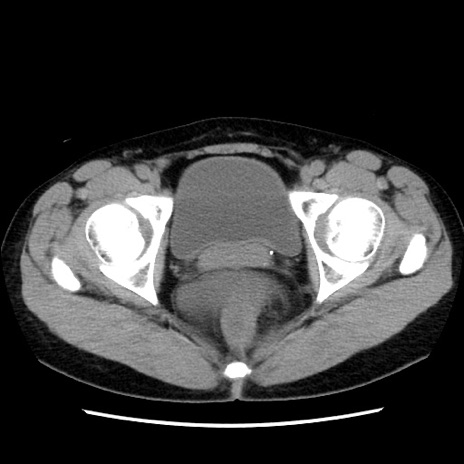

症例10(横断像)

【症例】 50歳代女性

【主訴】 腹痛

【現病歴】前日生レバーを食べた。今朝に排便あり。 昼前に突然発症の腹痛を生じ、当院救急外来を受診した。

【既往歴】 子宮筋腫にてで子宮全摘後

【身体所見】 意識清明、腹部:平坦、軟、下腹部やや左を中心に圧痛・反跳痛あり、筋性防御あり

【データ】WBC 7800、CRP 0.07